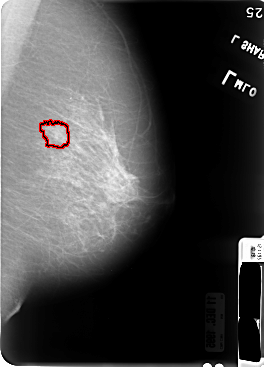

B_3046_1.LEFT_MLO

LEFT_MLO LINES 4760 PIXELS_PER_LINE 3424 BITS_PER_PIXEL 12 RESOLUTION 50 OVERLAY

FILE: B_3046_1.LEFT_MLO.OVERLAY

TOTAL_ABNORMALITIES 1

ABNORMALITY 1

LESION_TYPE MASS SHAPE IRREGULAR MARGINS SPICULATED

ASSESSMENT 4

SUBTLETY 3

PATHOLOGY MALIGNANT

TOTAL_OUTLINES 1

BOUNDARY